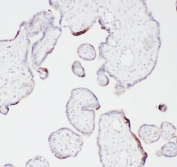

IHC staining of FFPE human placenta with Angiostatin K1-3 antibody. HIER: boil tissue sections in pH6, 10mM citrate buffer, for 20 min and allow to cool before testing.